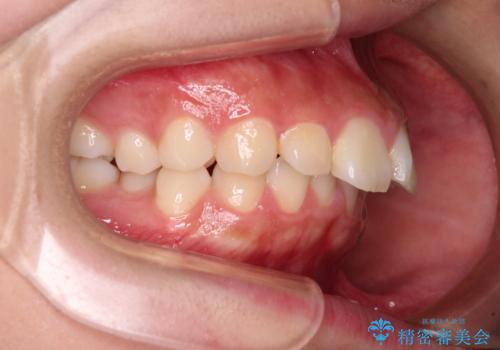

- 飛び出した上顎前歯と、閉じにくい唇、口元の突出した印象の横顔を気にして来院された患者様です。

骨格的な上顎前突であり、上下前歯の前後的な距離が大きいため、上顎は左右第一小臼歯を、下顎は左右第二小臼歯をそれぞれ2本抜歯することで前歯が接触するようにし、さらには奥歯の咬み合わせも、より理想的な状態へ近づけていくこととしました。

3年以上はかかる難症例であるため、表側のワイヤー装置にて治療を行うこととしました。

事前の予想通り、長期間を要する治療となりましたが、横顔の印象が劇的に変化し、患者様には大変満足していただきました。